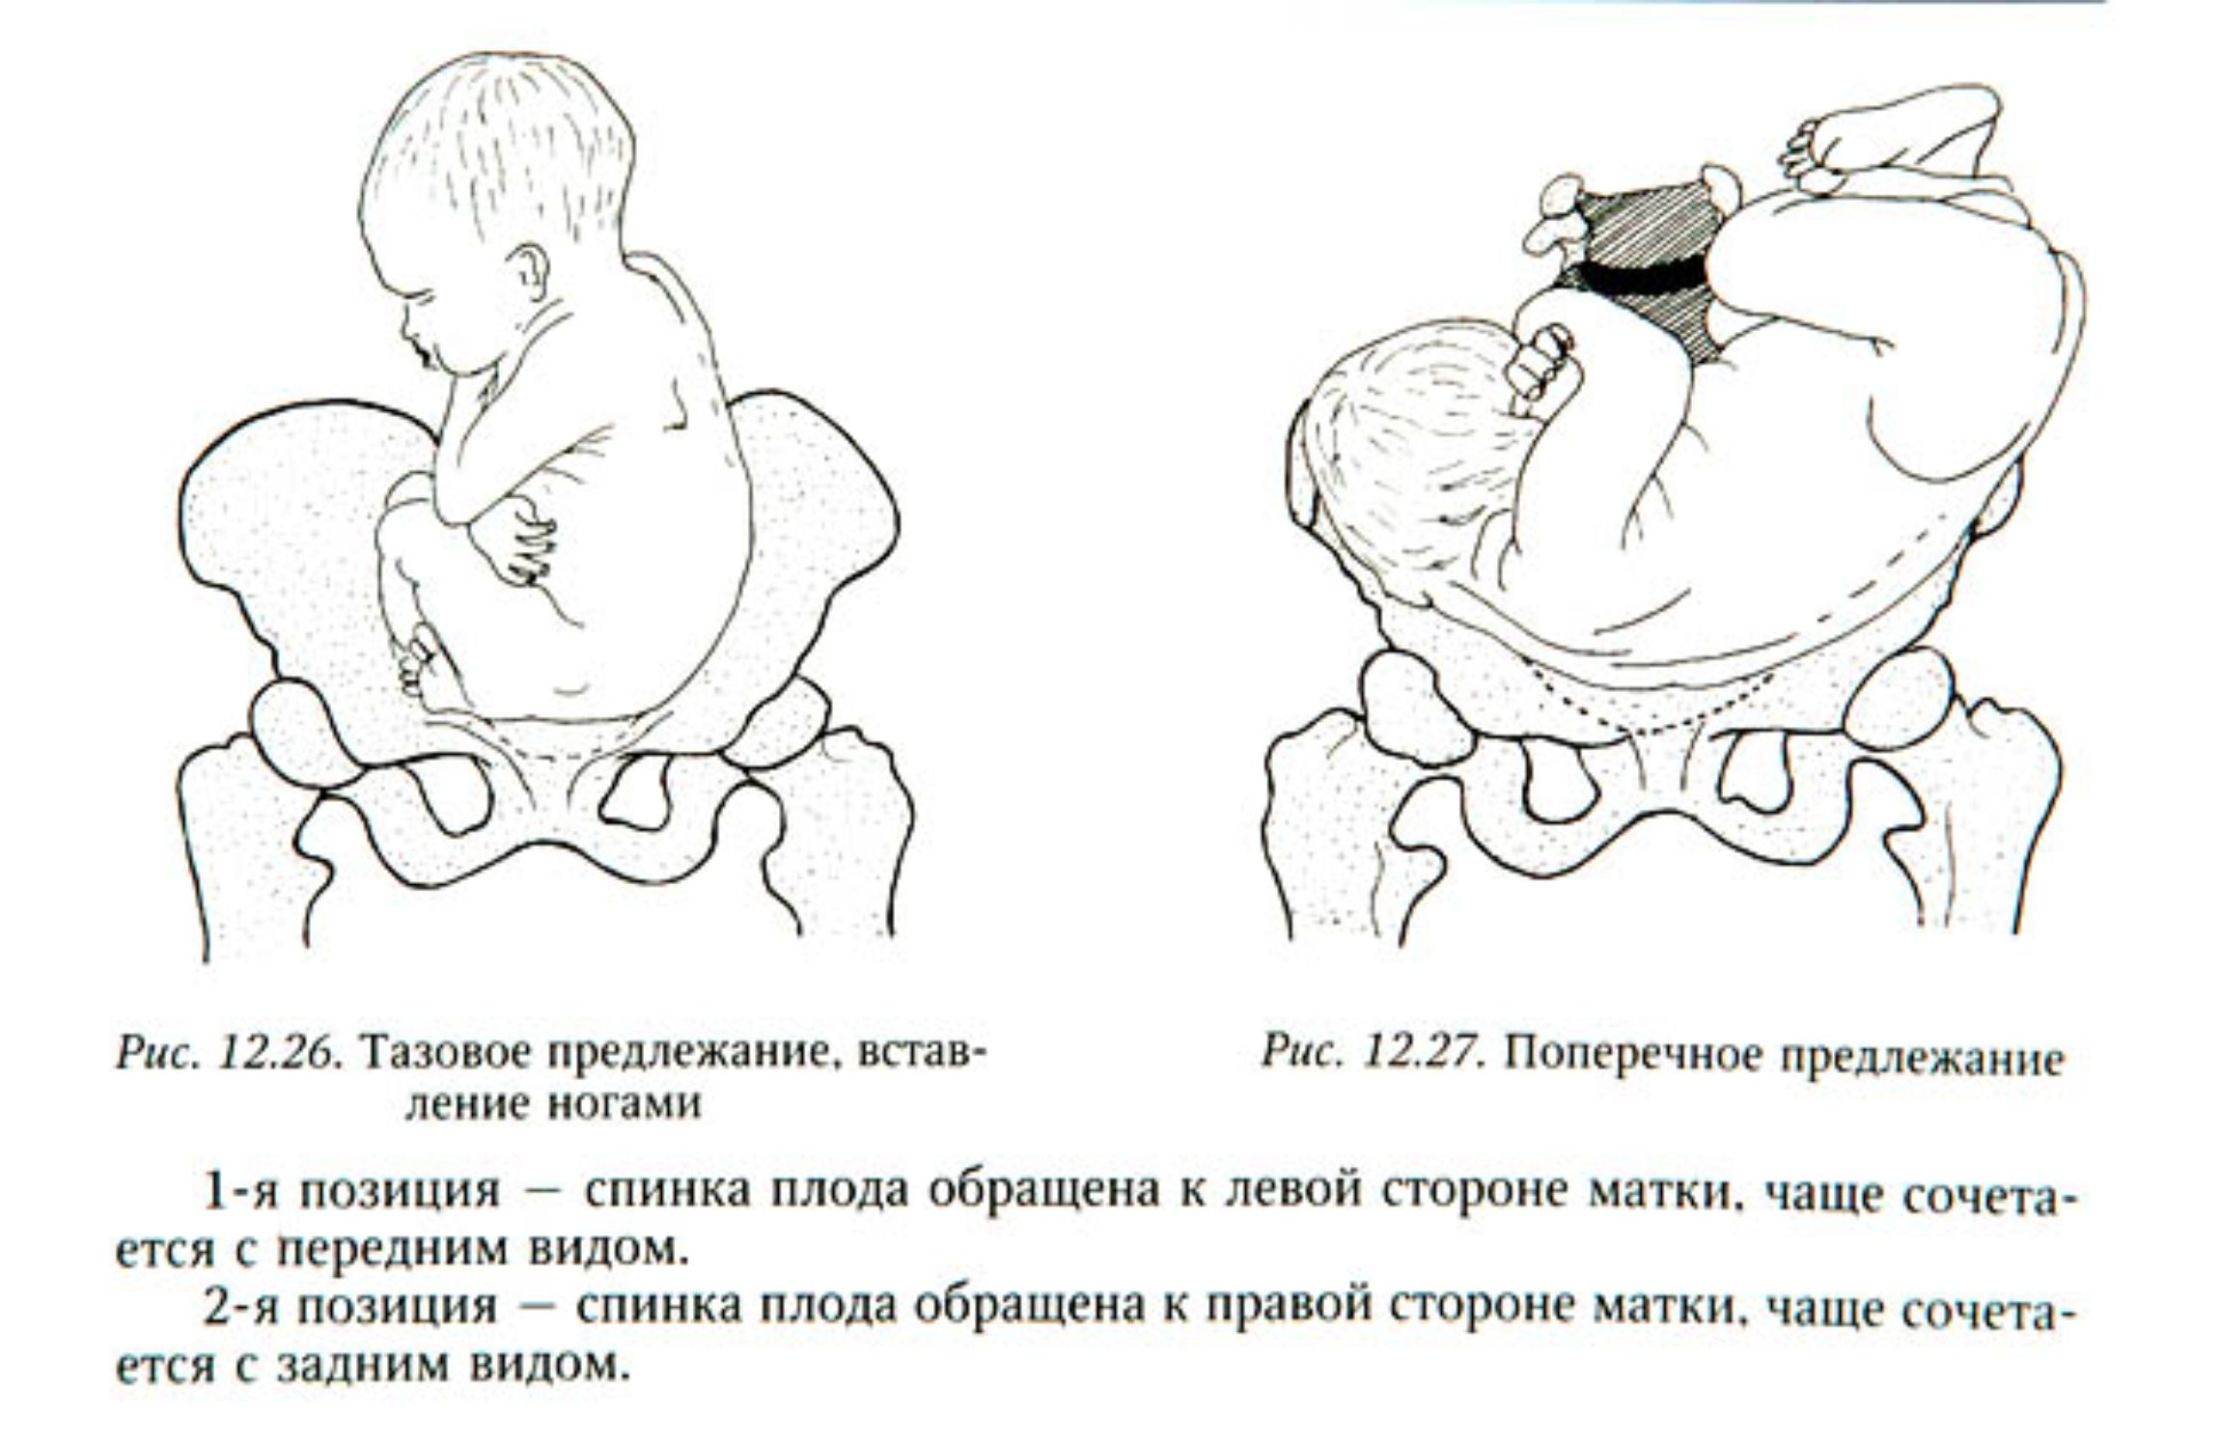

Breech.webp)

Живот с ягодичным предлежанием

External Cephalic Version(ECV) technique for Breech Baby